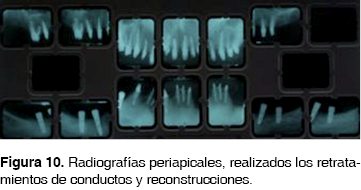

Se remitió al Departamento de Endodoncia para el tratamiento y retratamiento de los conductos. Una vez concluidos los tratamientos se colocaron postes reforzados con fibra de vidrio FRC Postec Plus ® (Ivoclar Vivadent) , cementados con resina para la reconstrucción de consistencia fluida para cementación adhesiva de postes endodónticos reforzados con fibra Multicore Flow (Ivoclar Vivadent) .

Los postes cementados fueron reconstruidos con otra resina de cuerpo pesado Multicore HB (Ivoclar Vivadent) y conformados con la guía de reconstrucción en acetato (Figura 10).

El FRC Postec Plus ® es un sistema de postes reforzados con fibra de vidrio, que ofrece una alta radiopacidad parecida a la de los postes metálicos. Con una radiopacidad de hasta 510% Al, se puede identificar claramente en las radiografías.